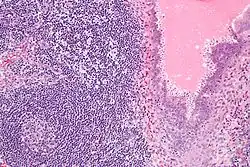

Endosalpingiosis is diagnosed by a pathologist on excision (e.g. biopsy).

It is characterized by cysts with tubal-type epithelium (e.g. ciliated epithelium) surrounded by a fibrous stroma. It is not often associated with hemorrhage.

Endosalpingiosis is occasionally found in lymph nodes, and may be misinterpreted as an adenocarcinoma metastasis.[5]